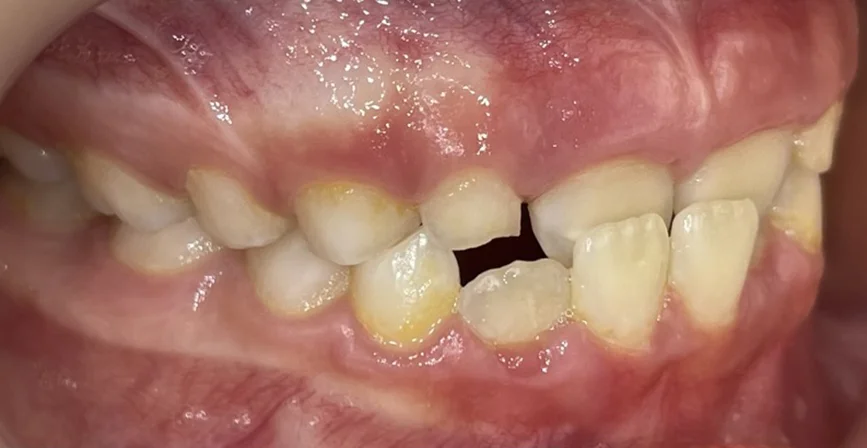

Търсейки детски ортодонт, пациентът дойде с основни оплаквания – “Долните зъби са пред горните” Кръстосаната захапка във фронта, затруднение при отхапване, нарушена естетика.

Кръстосана захапка във фронталния участък

Компресия на челюстите

Струпване и липса на място за пробива на постоянните зъби

Пациентката идва на първо посещение още когато е на 6- годишна възраст, наблюдава се пробив на централни долни резци зад млечните резци. Направена е екстракция на млечни резци 81 и 71.